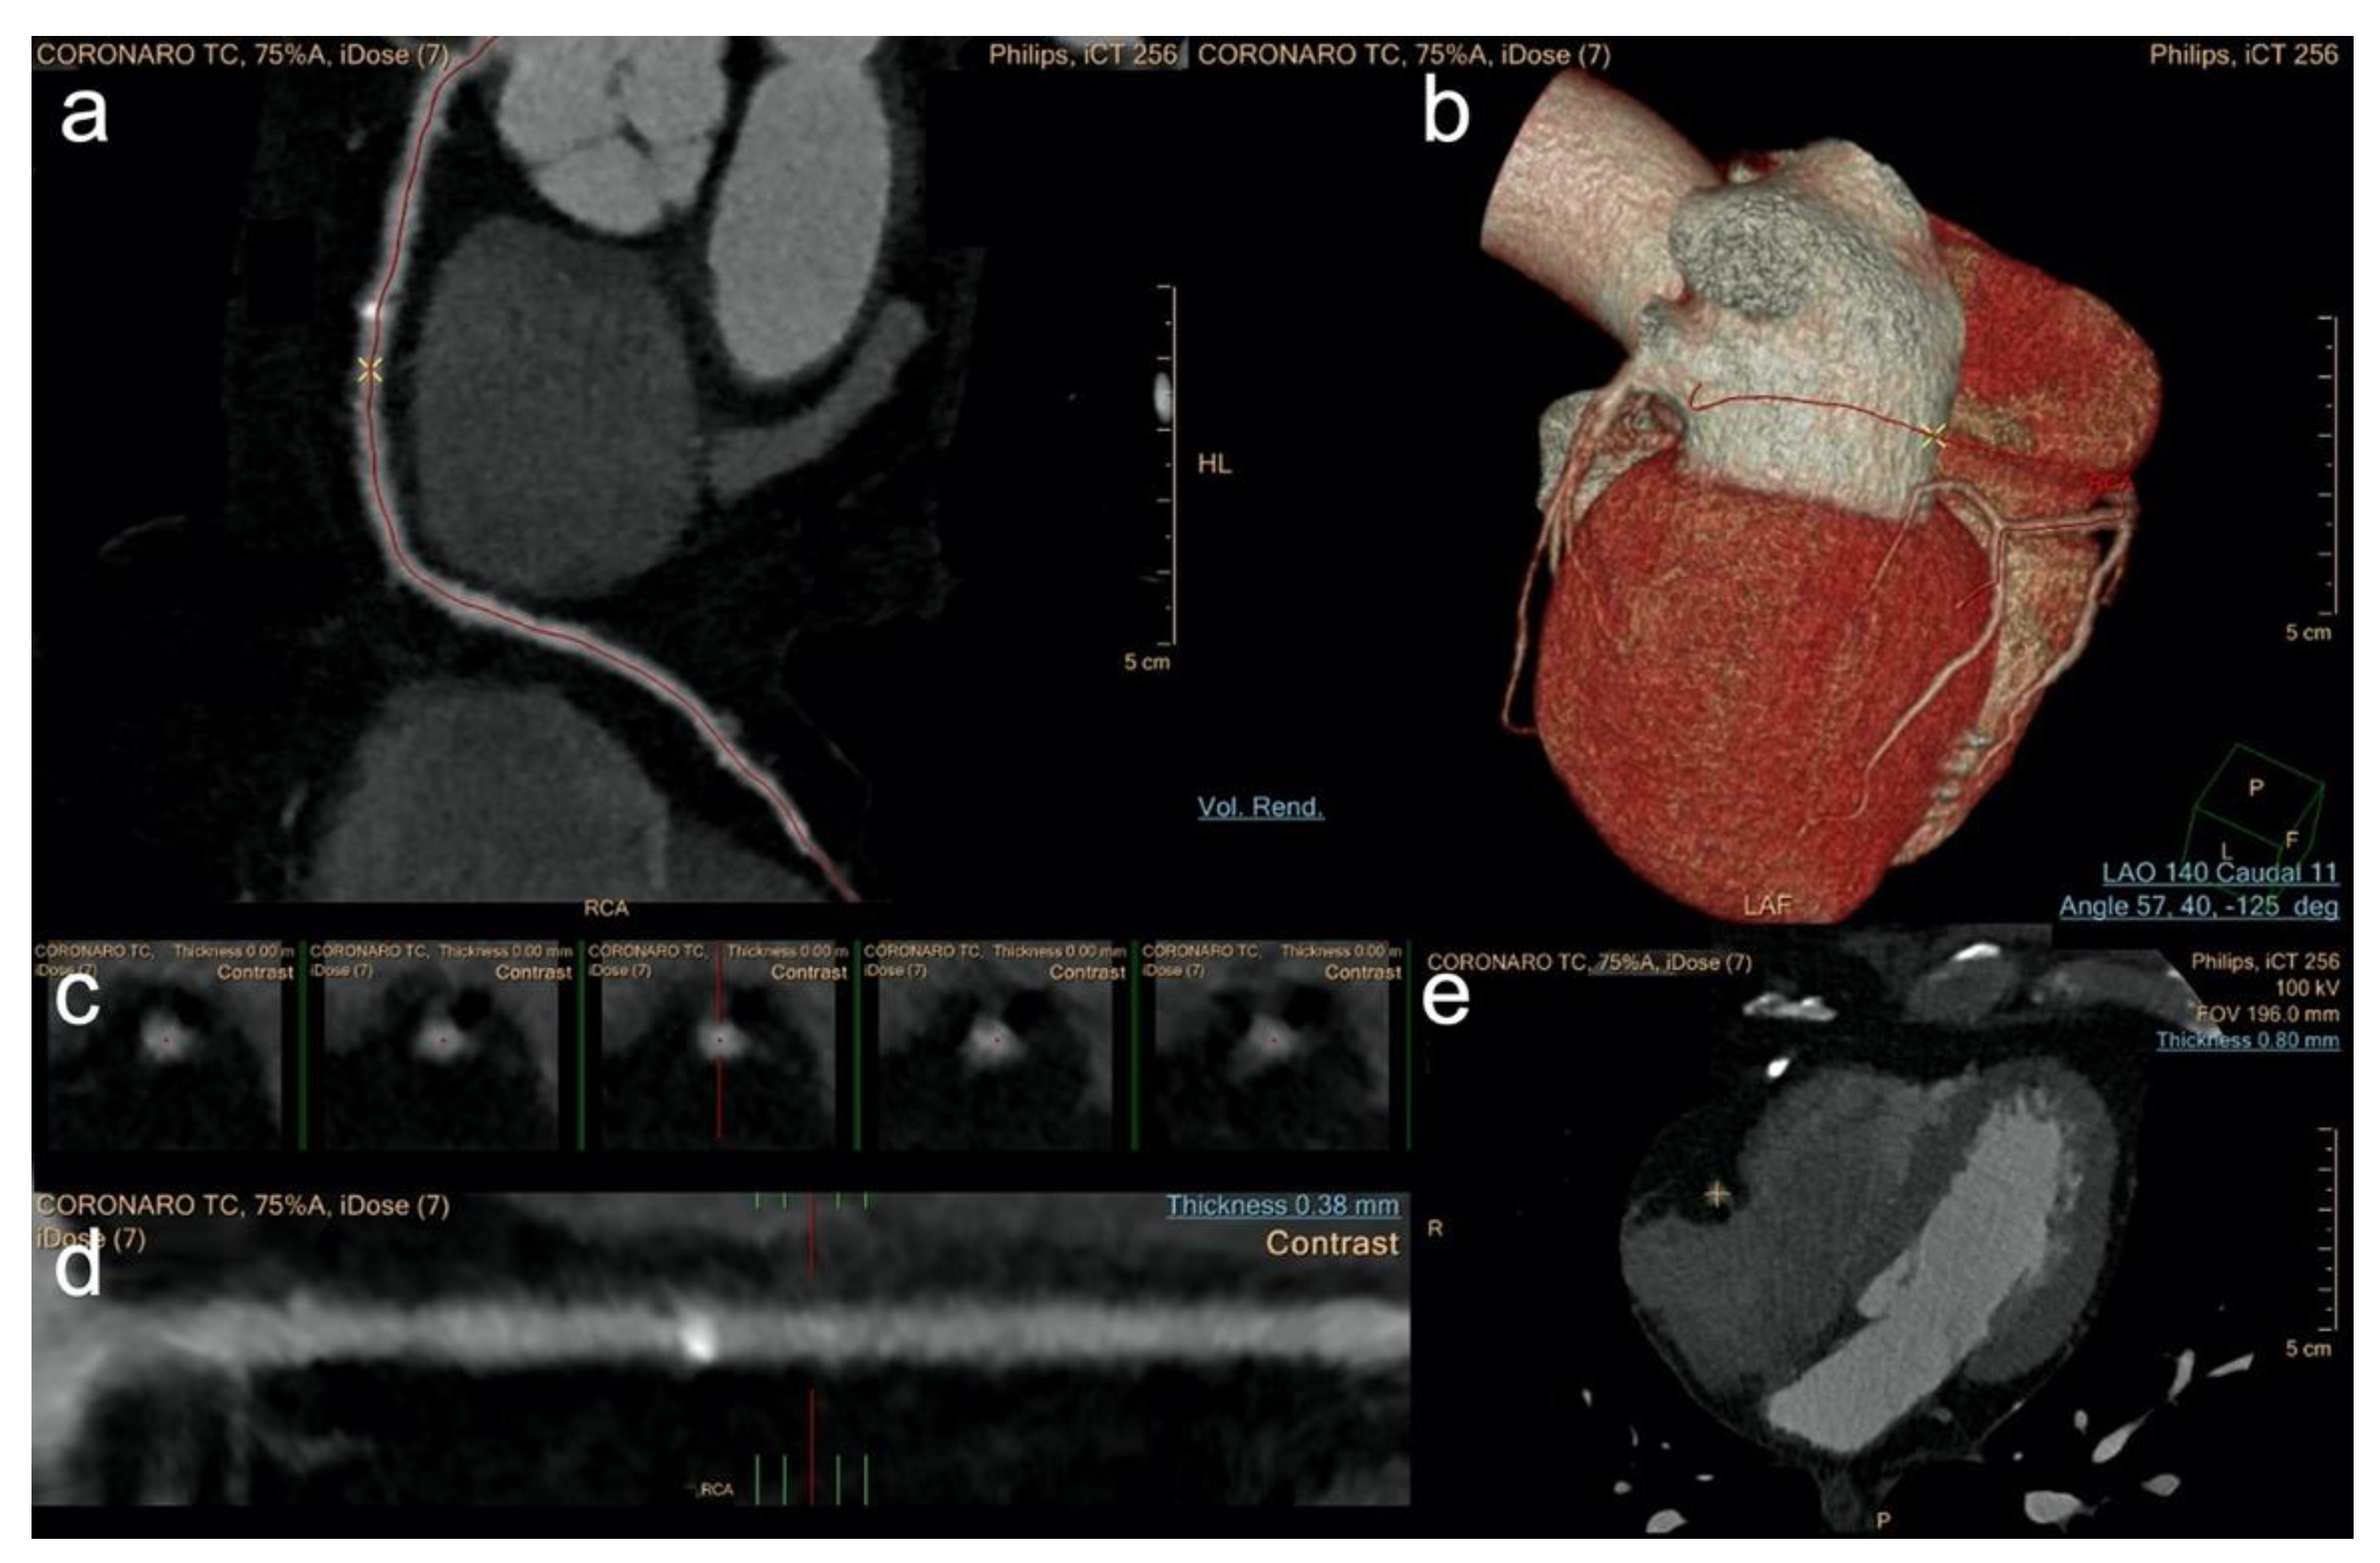

2.3. Image Post Processing—Group 1

2.5. Image Post Processing—Group 2